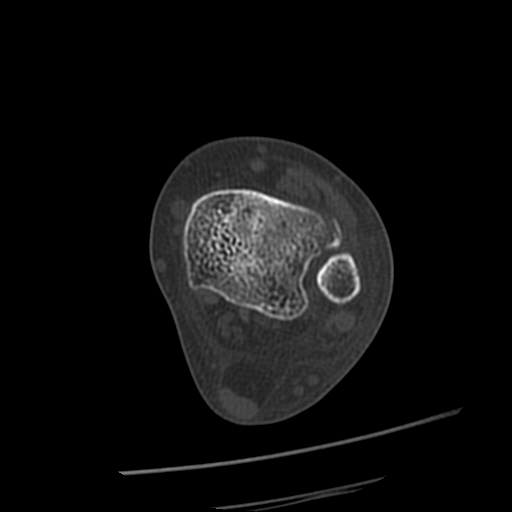

CT : avulsion fracture of distal tibia at distal tibiofibulat ligament insertion.